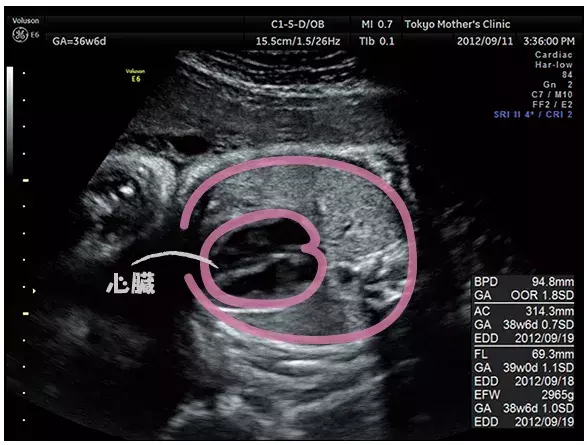

妊娠36週のエコー写真

赤ちゃんは子宮内で自由には動けないように。また、この頃の超音波検査は、通常の赤ちゃんの成長ぶりを確認するとともに、逆子などの理由で帝王切開になる可能性はないか、赤ちゃんの下がり具合や子宮の収縮などでお産が近づいているかなど、お産の進み方を推測します。

臨月になると体の一部しか見えません。成長の具合を最終チェックします。

この頃になるとエコー写真に写るのは体の一部だけ。大きな口を開けている横顔がくっきりと見えます。

写真提供:東京マザーズクリニック